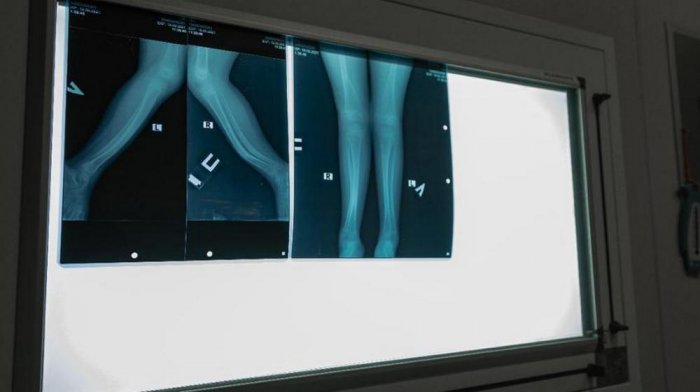

Прибывший из России детский ортопед Константин Жердев проводит в Актау мастер-классы для местных врачей. Гостем прооперировано 15 детей. Визит врача продлится до 9 сентября. Об этом сообщили в центре общественных коммуникаций Мангистау.

Фото ЦОК Мангистауской области